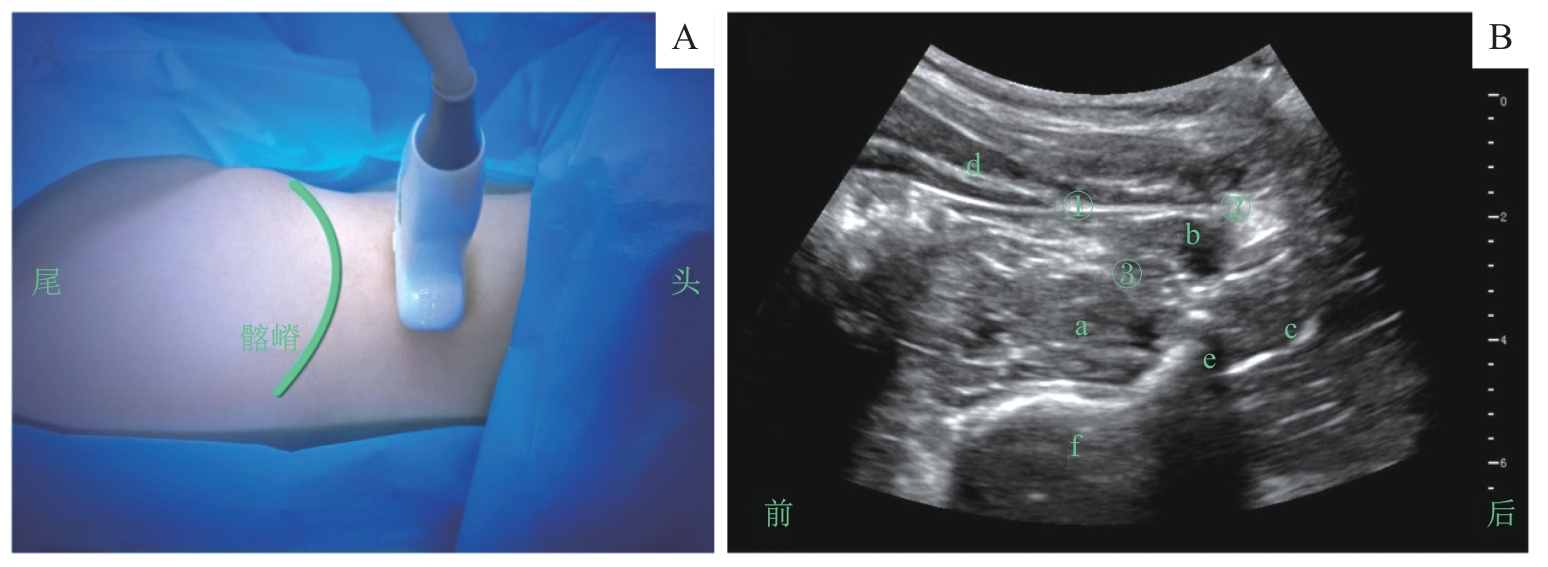

图6 腰方肌阻滞的超声定位和影像Note: A.超声探头体表扫描定位/Surface scanning for ultrasound probe positioning. B. 探头处于图A位置时的腰方肌超声影像/Ultrasound image of the quadratus lumborum obtained with the probe positioned as shown in figure A. a—腰大肌/psoas muscle; b—腰方肌/quadratus lumborum muscle; c—竖脊肌/quadratus lumborum muscle; d—腹肌/abdominal muscle; e—横突/transverse process; f—椎体/vertebral body; ① 腰方肌阻滞外侧点/needle insertion site for lateral quadratus lumborum block; ② 腰方肌阻滞后点/needle insertion site for posterior quadratus lumborum block; ③ 腰方肌阻滞前点/needle insertion site for anterior quadratus lumborum block.

Fig 6 Ultrasound positioning and imaging of the quadratus lumborum block